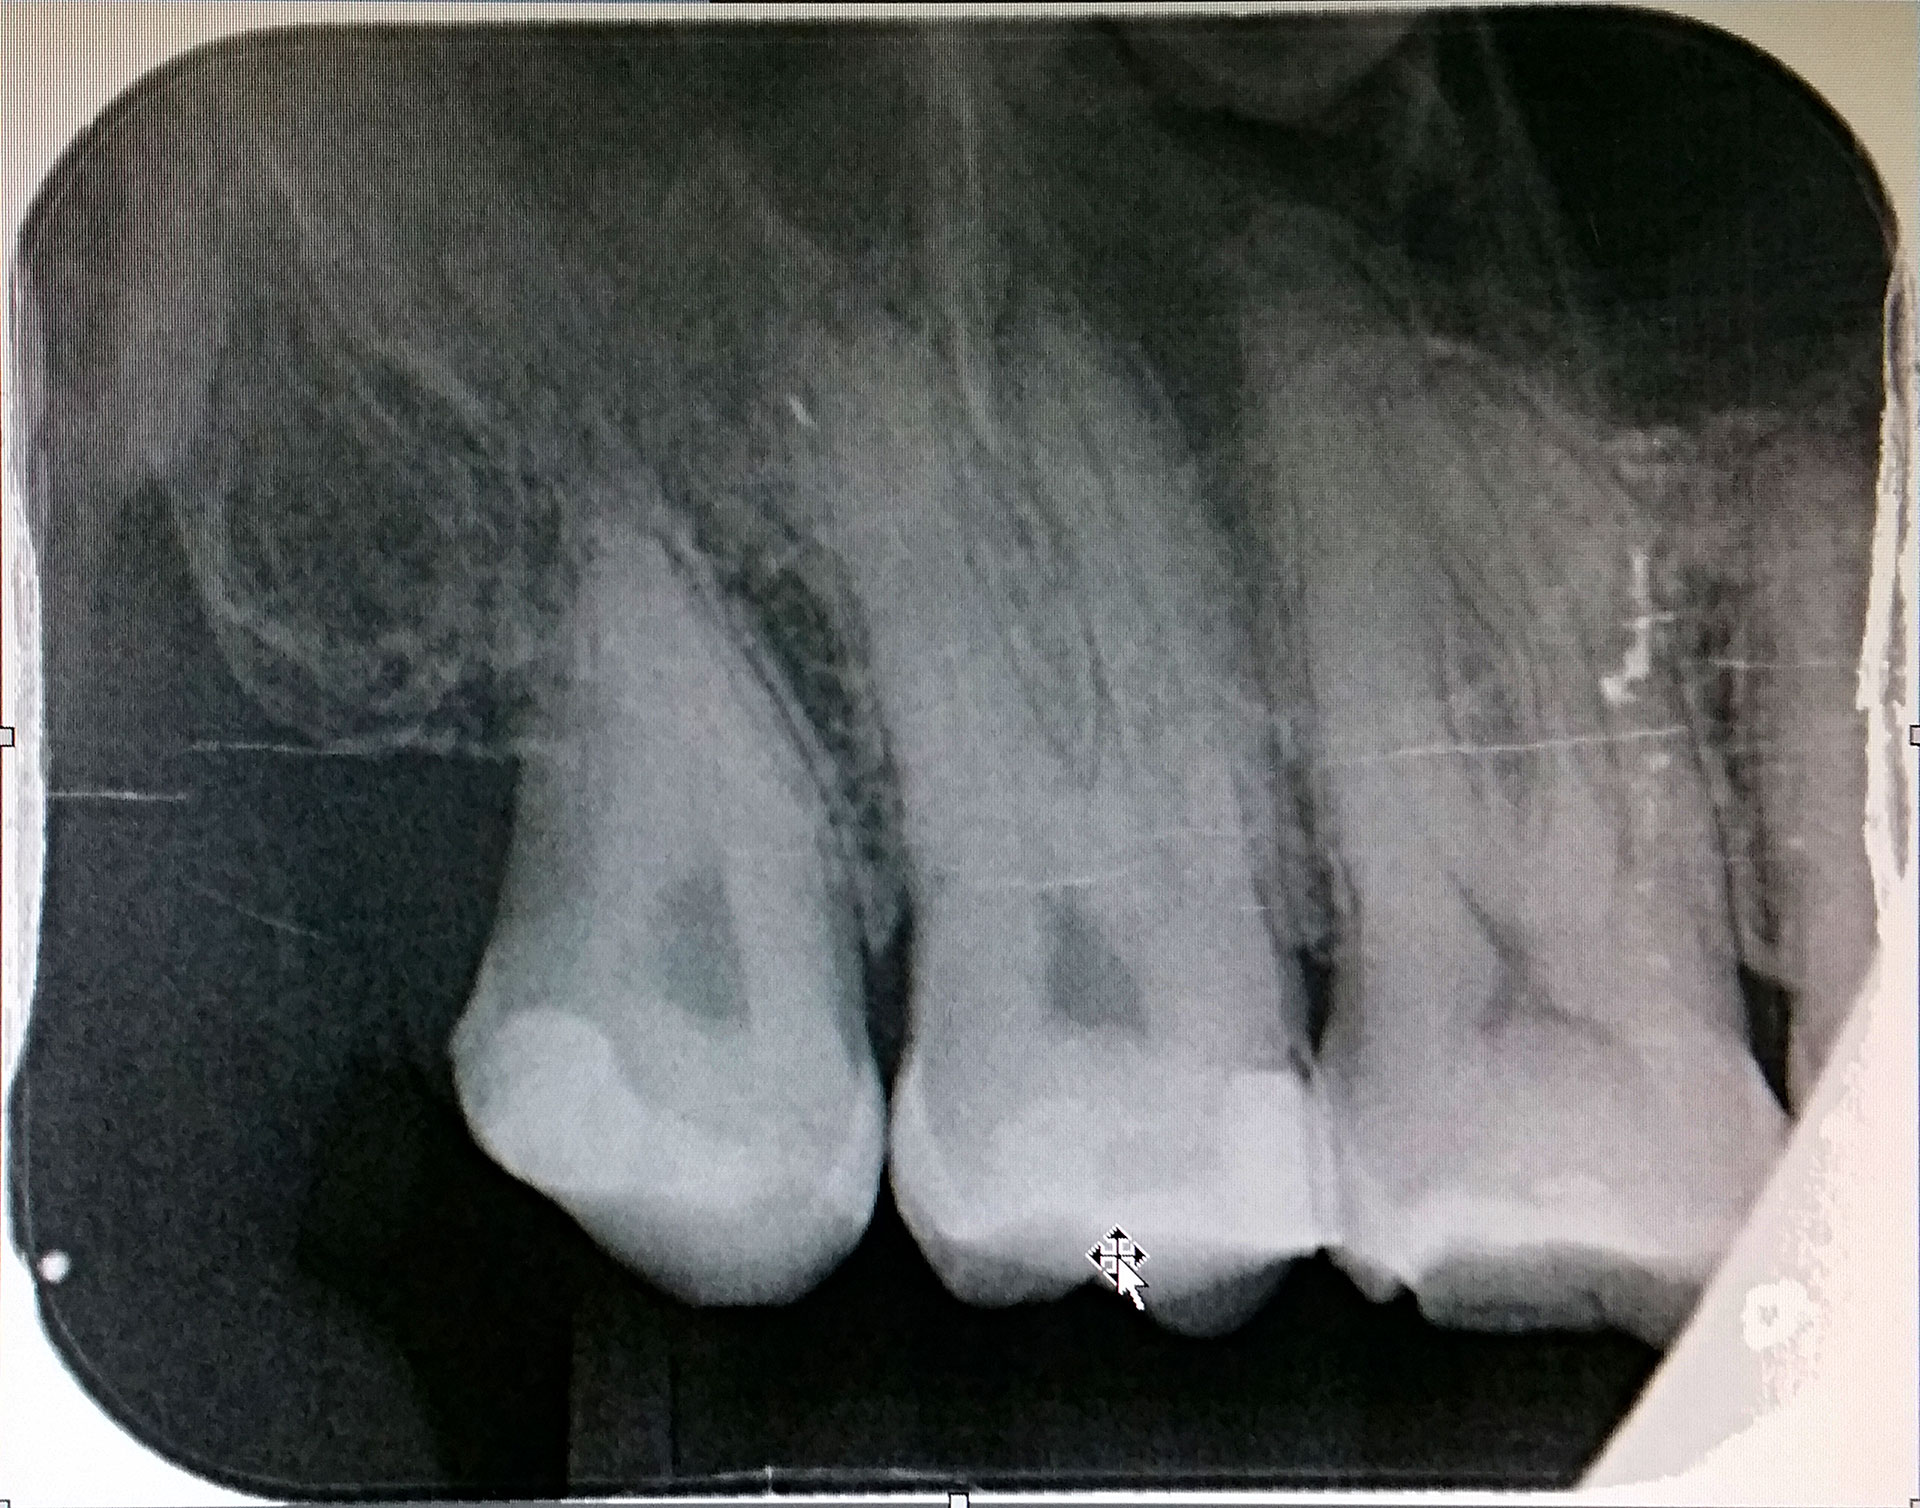

I saw Dr Jakub Lazorka, who took an x-ray and referred me to an endodontist—Dr Sam Tseng—to discuss root canal of the tooth. In the meantime he prescribed the same antibiotics I had last time—Amoxycillin 500mg and Metrogyl (metronidazole) 400mg, three times daily with food and absolutely no alcohol.